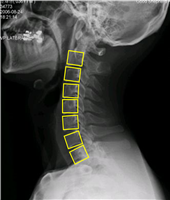

대표도면 데이터 종류 예시 데이터 종류 경추x-ray 흉추 MRI 흉추CT 예시

데이터 구성 경추 디스크의 높이

경추 각 추체에 대한 bounding boxT2 axial image에서 흉추5-6번 구간의 면적

어노테이션: txt